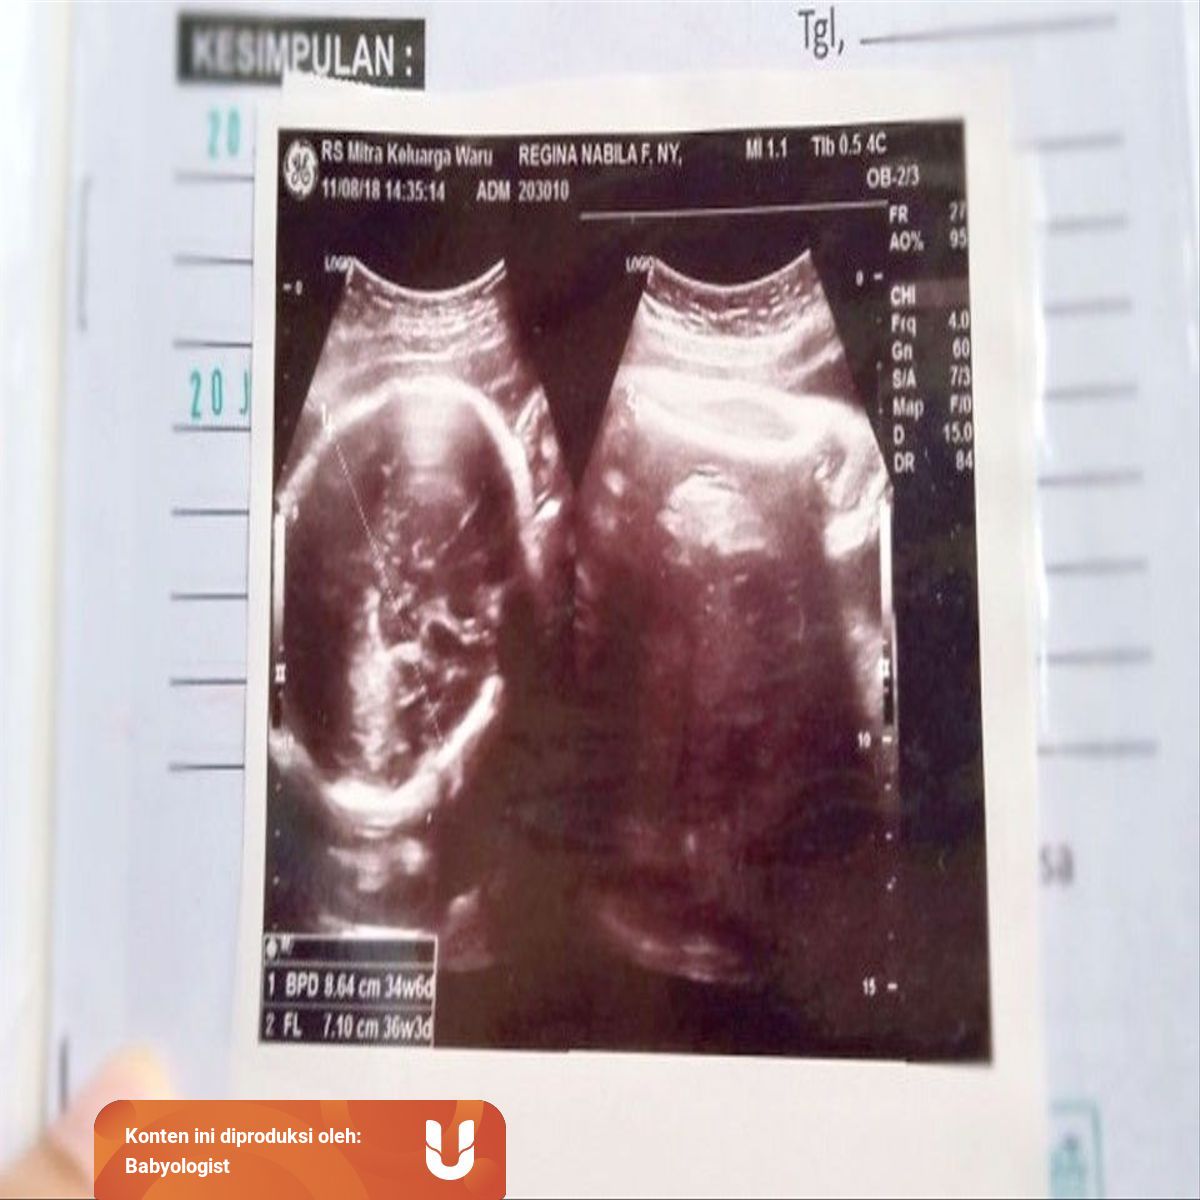

Hasil USG saya saat itu. Biparietal diameter is used to estimate fetal weight and gestational age. 834 34w0d FL.

USG terakhir dilakukan pada usia kehamilan 36-37 minggu. Usia kehamilan 31-32 minggu BPD 79-82 cm. Pemeriksaan awal sama seperti sebelumnya Minyu.

Untuk lingkar kepala bayi atau BPD sendiri antara usia 33-37 minggu dapat berkisar antara 83-95 cm pada kondisi saat ini bisa sedikit lebih besar dari normal. Persalinan yang normal umumnya terjadi saat usia kandungan 37-42 minggu kurang dari 37 minggu prematur 42 minggu postmatur. BPD umumnya digunakan untuk mengukur janin saat memasuki trimester dua atau tiga.

Usia kehamilan 37-40 minggu BPD 95 cm. Cara Membaca Hasil USG. Beberapa istilah yang umum ada di hasil foto USG antara lain.